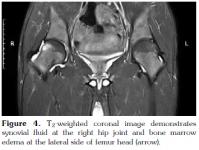

Synovitis is an important finding in the early involvement of the hip joint in AS, and it characterized by mild to moderate thickening of the synovial membrane and increased joint fluid on MRI.[1] In our study, eight patients (34.7%) showed unilateral synovial fluid (Figure 4). Three patients, on the other hand, demonstrated bilateral synovial fluid. These findings were found to be statistically significant when compared with those of the control group. No intravenous contrast agents were used in our study; but we think that the administration of gadolinium may contribute to the demonstration of the inflamed synovial membrane.